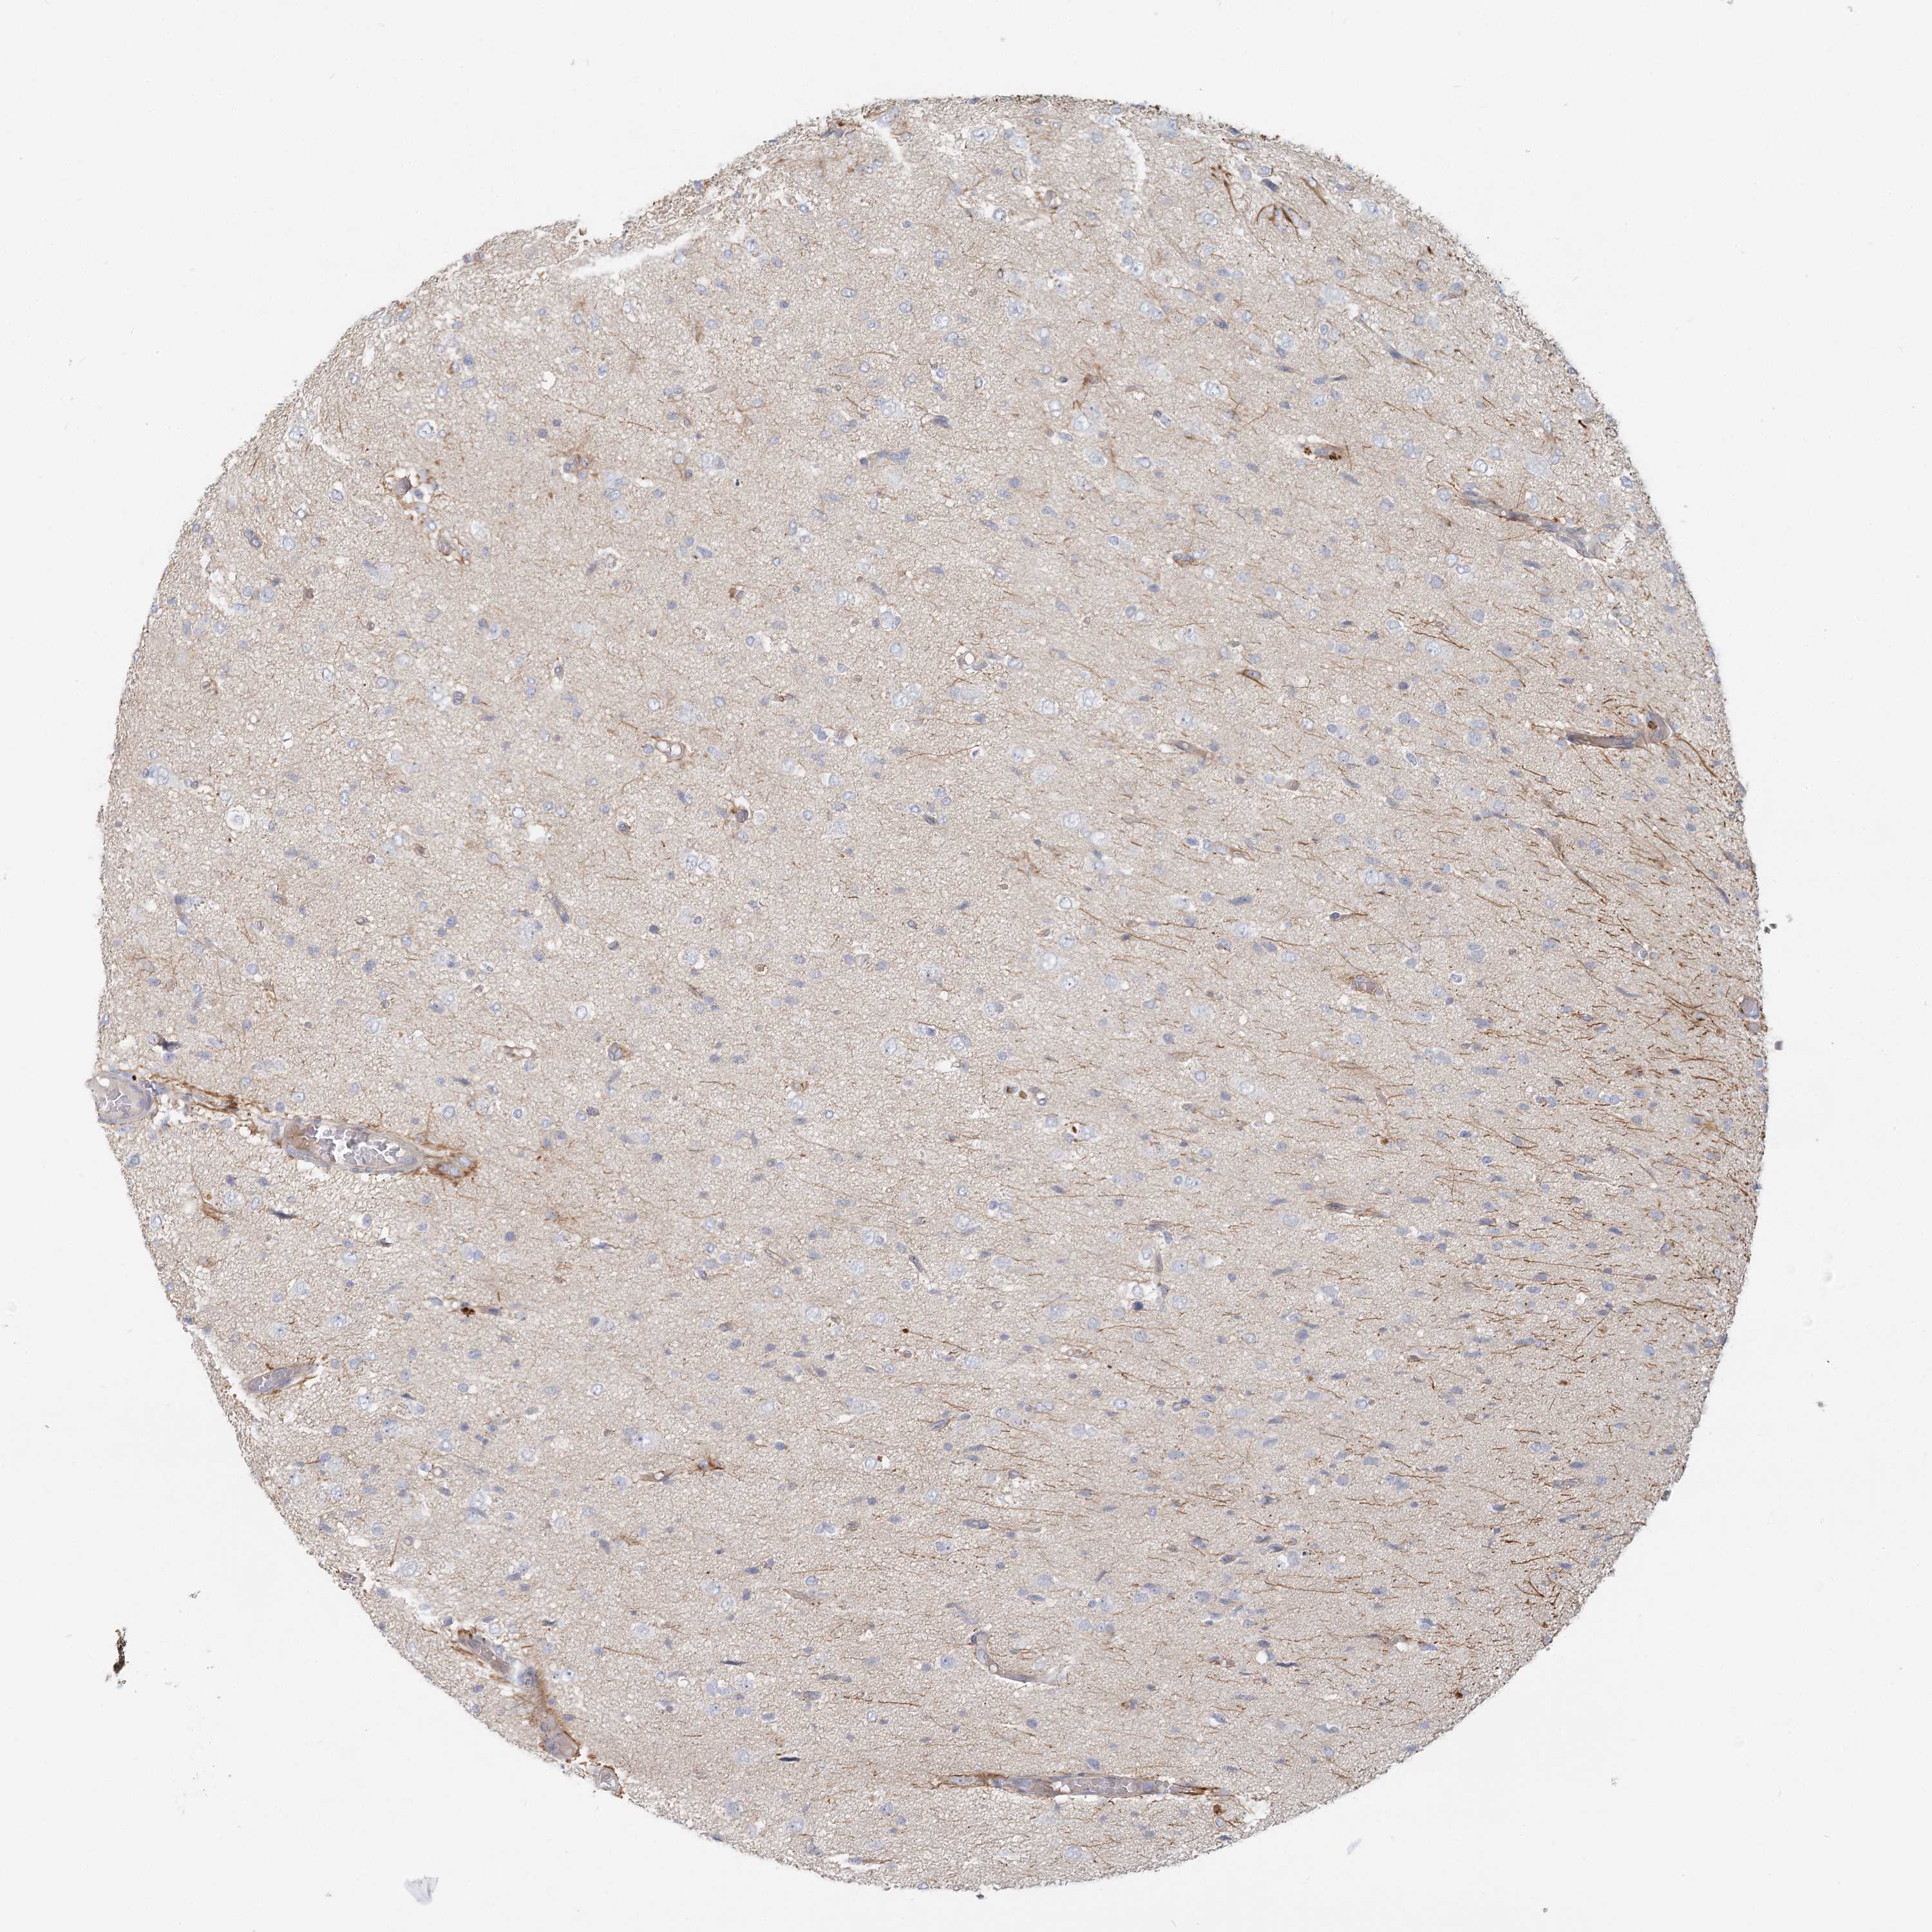

GLIOMA - Protein expressioni

A mouse-over function shows sample information and annotation data. Click on an image to view it in a full screen mode. Samples can be filtered based on level of antibody staining by selecting one or several of the following categories: high, medium, low and not detected. The assay and annotation is described here.

Note that samples used for immunohistochemistry by the Human Protein Atlas do not correspond to samples in the TCGA dataset.

Antibody stainingi

Antibody staining in the annotated cell types in the current human tissue is reported as not detected, low, medium, or high, based on conventional immunohistochemistry profiling in selected tissues. This score is based on the combination of the staining intensity and fraction of stained cells.

Each image is clickable and will lead to virtual microscopy that enables deeper exploration of all samples and also displays staining intensity scores, fraction scores and subcellular localization as well as patient and tissue information for each sample.

Antibody HPA037878

Staining

High

Medium

Low

Not detected

Intensity

Strong

Moderate

Weak

Negative

Quantity

>75%

75%-25%

<25%

None

Location

Nuclear

Cytoplasmic/membranous

Cytoplasmic/membranous,nuclear

Glioma, malignant, High grade

Glioma, malignant, Low grade

Glioblastoma, NOS